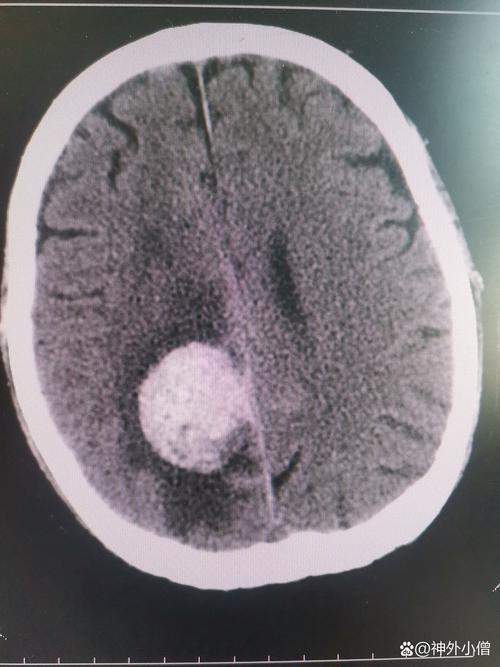

脑梗死 (Cerebral Infarction / Stroke)

(图片来源网络,侵删)- 俗称“中风”,指因脑部血管堵塞,导致局部脑组织因缺血、缺氧而发生坏死。

(图片来源网络,侵删)

- CT扫描:

- 早期(6小时内)可能看不出明显异常,或者仅见密度轻微降低。

- 24-48小时后,梗死区域和周围的水肿带会表现为低密度区域,边界不清,像一个“模糊的阴影”。